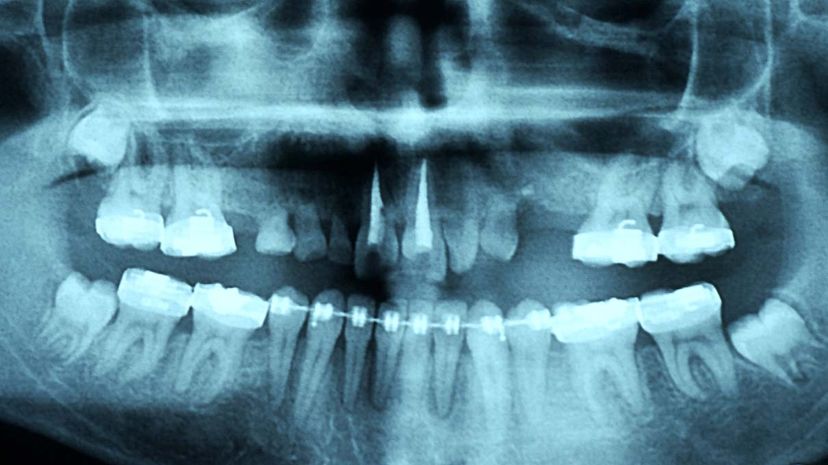

How To Pull A Loose Tooth Out Adults. In kids, this process is perfectly normal but sometime such a tooth become irritating for kid also. Loose teeth in kids are a perfectly normal, if somewhat irritating, part of growing up. Mix a tablespoon of salt in 6 ounces of warm water and swish vigorously around in your mouth. Learn how to pull a tooth safely at home with this tutorial. If the tooth is impacted the dentist will cut away gum and bone tissue that cover the tooth and then using forceps grasp the tooth and gently rock it back and forth to loosen it from the jaw.

Now we have a wiggler, a tooth that is hanging tight enough to be a slippery one to pull out barehanded, but loose enough to still get tugged out with some creativity. This will loosen the tooth more over time. Vu helps adults and kids of all ages get over their anxiety with dental phobia. These methods are quite easy to apply and are likely going to help your you can easily trap a loose tooth inside of a hard food if you don't want to wiggle it out. It wants to come out, but we want to get it done creatively. Tooth mobility is normally a warning for a dental problem, which may need immediate attention. Pull the tooth out by hand if your child's tooth is already very loose, use a wash cloth to pull it out by hand. Mix a tablespoon of salt in 6 ounces of warm water and swish vigorously around in your mouth.

How to pull a tooth out adults. I have a horrible cavity. Now we have a wiggler, a tooth that is hanging tight enough to be a slippery one to pull out barehanded, but loose enough to still get tugged out with some creativity. The following factors are often responsible for looseness in hardened plaque, known as tartar, causes the gums to pull away from the teeth, creating gaps that. There are other ways that many people have tried. Think of this as a kind of cast for your tooth. If the tooth is impacted the dentist will cut away gum and bone tissue that cover the tooth and then using forceps grasp the tooth and gently rock it back and forth to loosen it from the jaw. Loose tooth always takes some time till it fallout. If your child has a loose tooth and you are in confusion whether to pull out the loose tooth or not, then you should go through this article. Pull it out with dental floss. Loose teeth tend to start out with a subtle wiggle. You can consider pulling of a tooth if the tooth is very loose & the child is impatient to deal with the inconvenience caused by loose tooth. My son has a loose tooth.

I can almost guarantee that he will snap off the tooth at how to pull a loose tooth? In adults, however, loose teeth may be a cause for concern. Baby teeth and teeth that are loose due to. Loose teeth tend to start out with a subtle wiggle. Loose tooth always takes some time till it fallout. Loose teeth, especially if it's already dangling, have a better chance of getting pulled out successfully. Wiggle your tooth back and forth and up and down. Pull it out with dental floss. Loose teeth, either in children or adults, are truly irritating. Tooth mobility is normally a warning for a dental problem, which may need immediate attention. Loose teeth in kids are a perfectly normal, if somewhat irritating, part of growing up. If it's a primary tooth, the permanent tooth coming in behind it will push it out on its own. All it takes is biting into something chewy or otherwise firm.

Before pulling out your tooth, you should loosen it up a bit more. How to pulling a loose molar! These can also lead to loose teeth. How long does a loose tooth take to heal? Pull the tooth out by hand if your child's tooth is already very loose, use a wash cloth to pull it out by hand. If you want to pull out a loose tooth with no pain, this is what you do. If you want to know how to save a loose tooth from falling out, it's fairly simple. If your children are afraid, encourage them and say that everyone goes through this. Loose teeth, especially if it's already dangling, have a better chance of getting pulled out successfully. If the tooth is impacted the dentist will cut away gum and bone tissue that cover the tooth and then using forceps grasp the tooth and gently rock it back and forth to loosen it from the jaw. If you have a loose permanent tooth or teeth you need to see your dentist as soon as possible. I can almost guarantee that he will snap off the tooth at how to pull a loose tooth? Be sure your child washes his hands thoroughly with antibacterial soap to remove as many germs as possible before he.